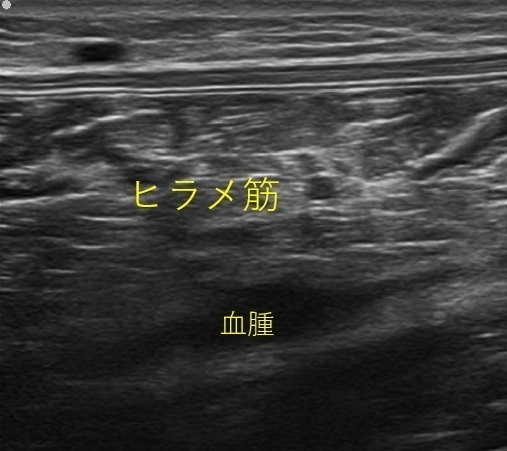

41歳・男性 陸上競技者

以前から腓腹筋の肉離れを繰り返していましたが、長距離走の際にヒラメ筋に疼痛がみられた方です。

正常ではみられないヒラメ筋内の低エコー像(黒く映る部分)がみられ、液体成分が貯留している様子が観察できました。

下腿三頭筋の肉離れは再発が多いため段階的な筋力トレーニングを行い復帰を目指していきます。

ヒラメ筋損傷(ヒラメ筋内に血腫がみられる)